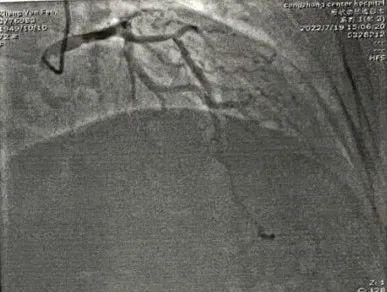

冠脉造影

冠脉硬化

LAD病变

冠脉处理前

冠脉处理后

冠脉处理前后对比